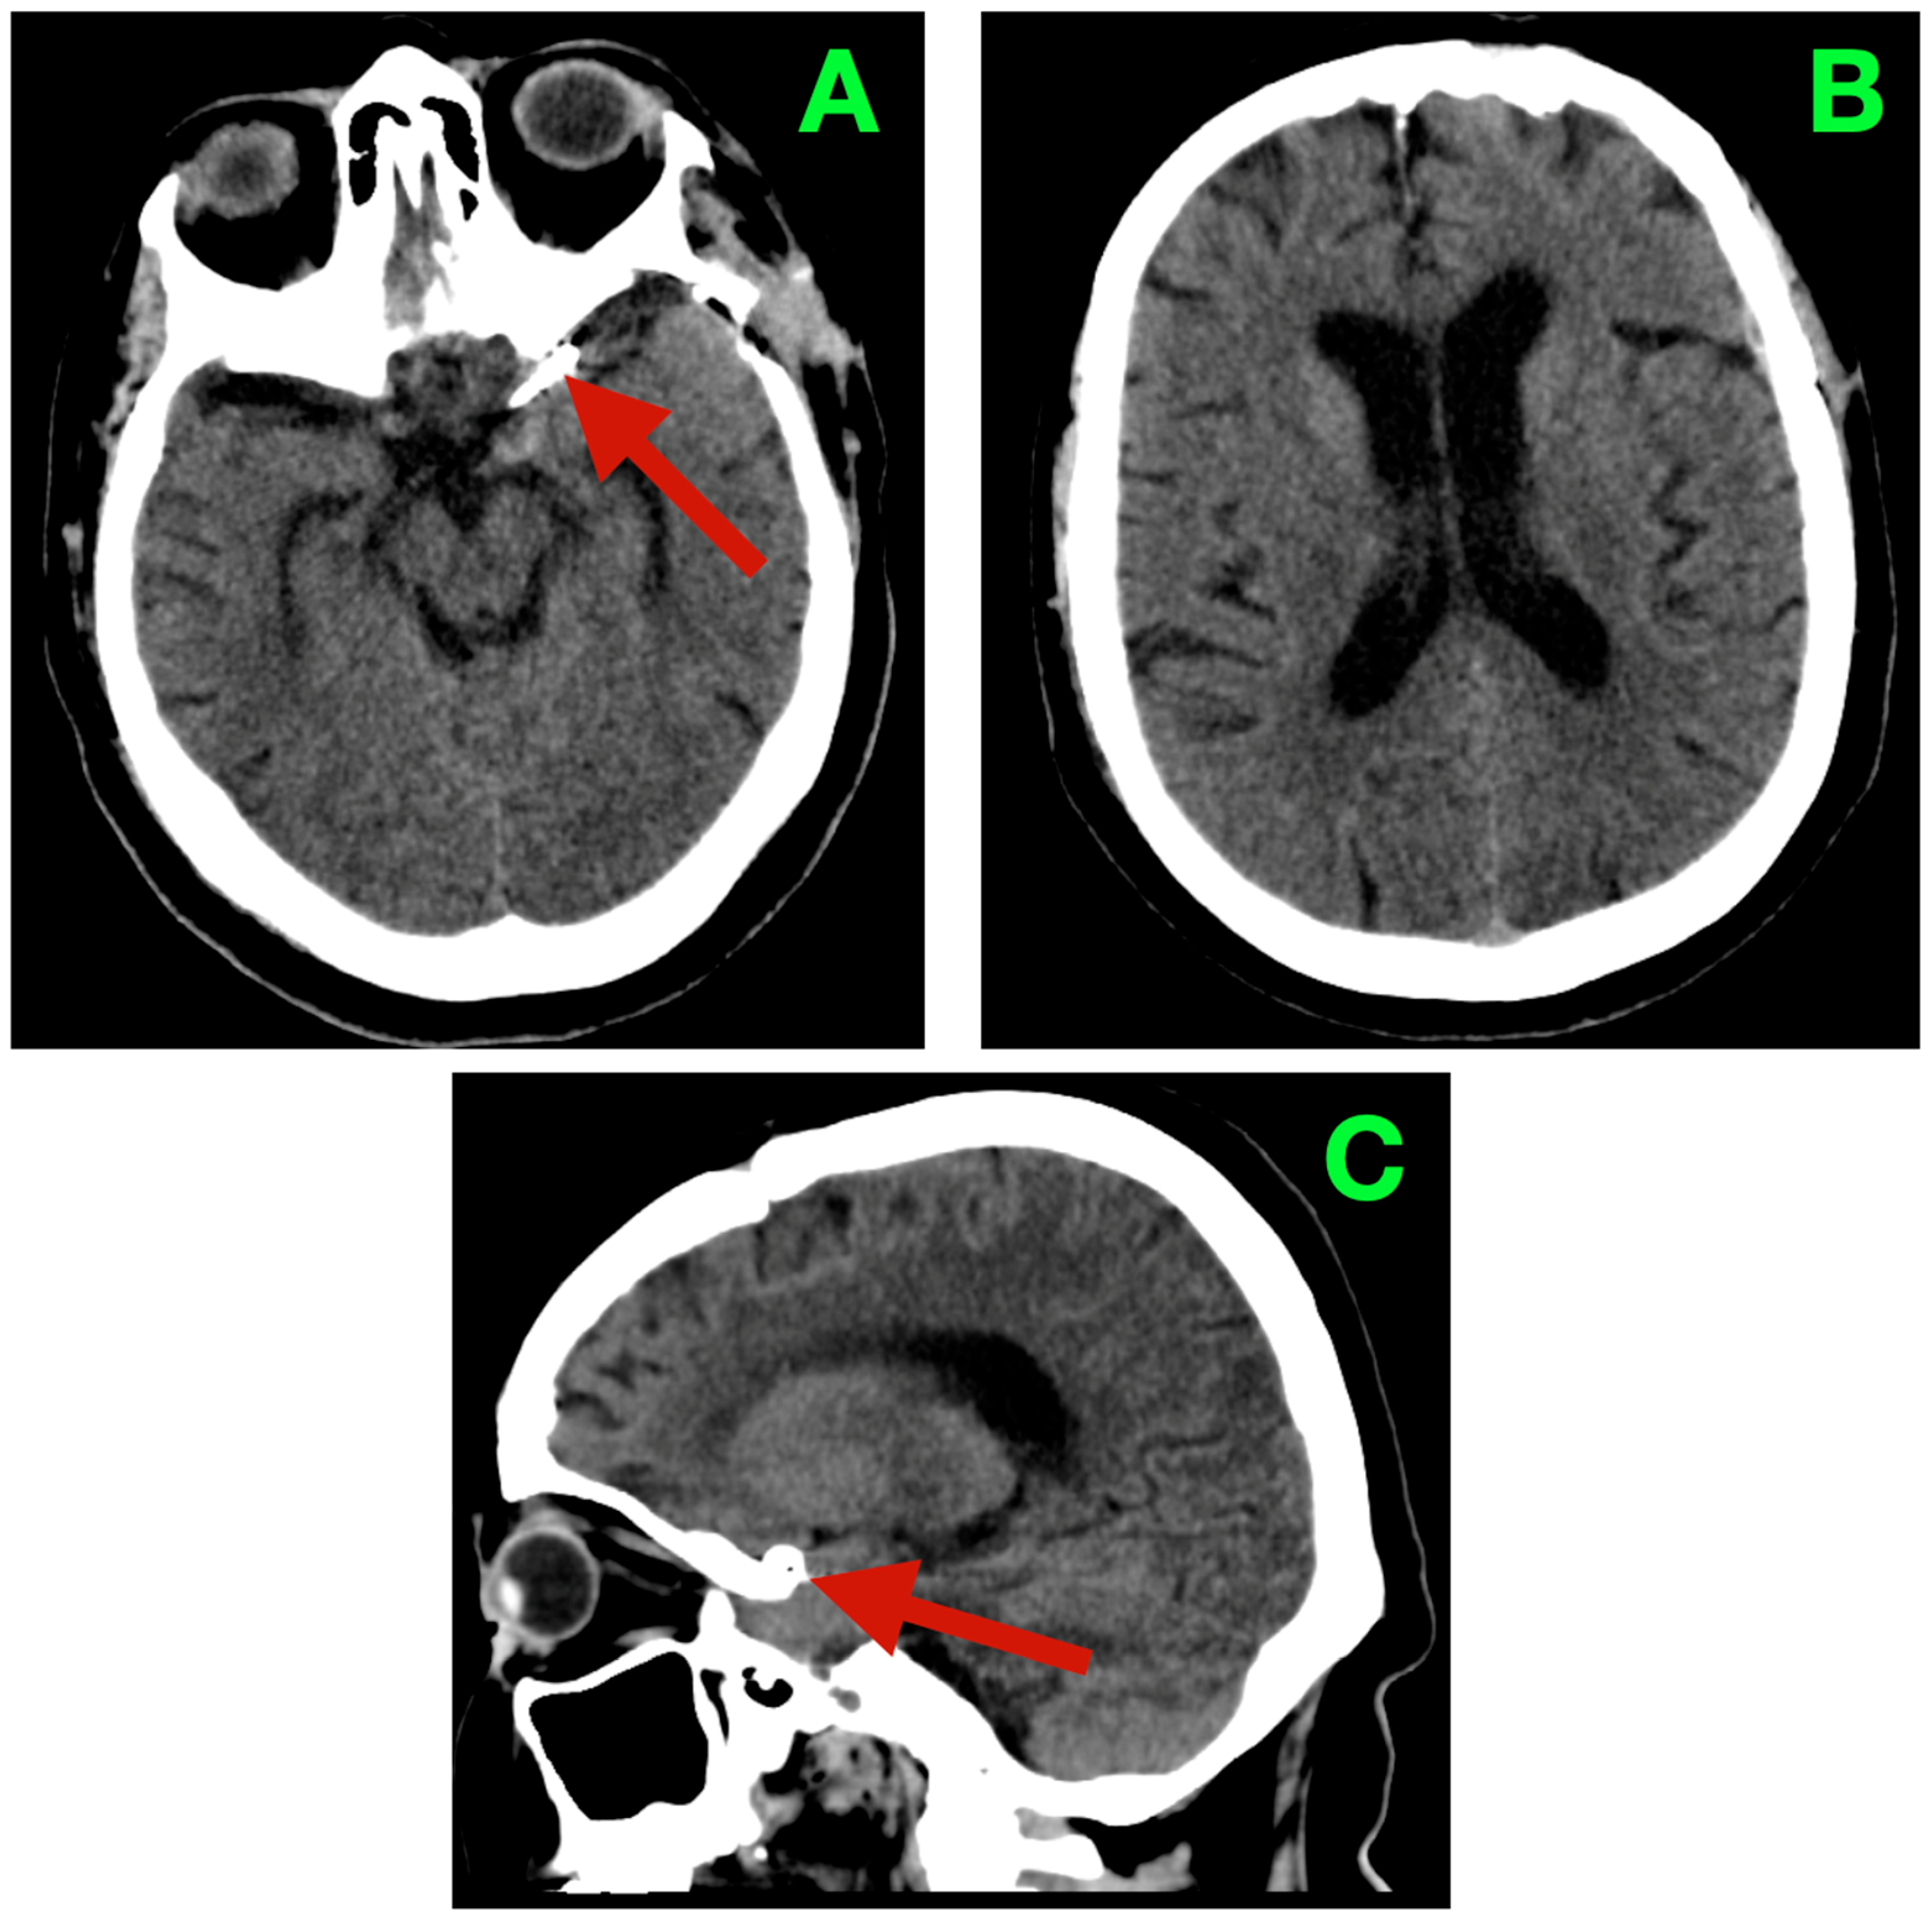

At 24 h postoperatively, follow-up DSA was performed to evaluate the technical success of the procedure. Complete exclusion of the aneurysm was verified, as was preservation of the ICA caliber and the patency of both the PCoA and AChA. Symmetrical hemispheric opacification was observed, and no evidence of delayed transit was noted (Figure 3).

Figure 3.

Early postoperative digital subtraction angiography of the left ICA. (A): AP projection: no residual filling at the ICA–PCoA junction; the clip line corresponds to the neck plane. (B): Oblique working view: caliber-preserved supraclinoid ICA with a free PCoA origin and smooth contour. (C): AP run: normal hemispheric opacification without pruning or delayed transit—no angiographic vasospasm. (D): Lateral projection: complete obliteration at the reconstruction site with an uncompromised anterior choroidal course.

At three months, she returned headache-free and fully functional, with no visual or visual–motor sensations, complaints related to gaze or other sensory complaints. Tandem gait was steady; coordination was fluid; there were no exertional triggers or sentinel pains. At that visit, the non-contrast head CT showed a stable clip complex, centered in the left suprasellar/carotid–optic cistern; patent basal cisterns; age-appropriately sized ventricles without ventriculomegaly or transependymal seepage; and without hemorrhagic or ischemic character alterations (Figure 4). These findings aligned with her normal, walks out of health care and an appropriate health-related quality of life (HRQoL).

Figure 4.

Three-month non-contrast cranial CT. (A): Axial basal slice: stable clip complex in the left suprasellar/carotid–optic cistern (arrow); basal cisterns patent; no hemorrhage. (B): Axial high-convexity slice: ventricular configuration normal with no ventriculomegaly or transependymal seepage. (C): Midline sagittal reconstruction: unchanged parasellar clip position (arrow), no extra-axial collection and no parenchymal hypodensity to suggest delayed ischemia.